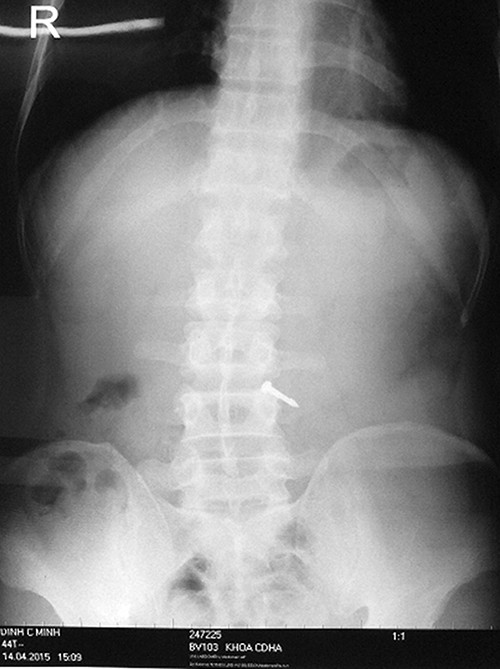

Gần hết giờ làm việc buổi chiều ngày thứ 3 (14/4/2015), anh được đưa thẳng vào Khoa Nội Tiêu hóa, Bệnh viện 103 cấp cứu sau 1 tiếng xảy ra vụ việc, trong tình trạng vẫn tỉnh táo, tiếp xúc tốt, đau bụng âm ỉ, có lúc tức nhiều vùng thượng vị, bụng mềm hoàn toàn, trung tiện được. Trên phim X-quang bụng không thấy liềm hơi dưới cơ hoành, có dị vật kim loại 1 đầu nhọn, 1 đầu tù nằm ở vị trí ngang với đốt sống L3.

Phim X-quang bụng của bệnh nhân M. có dị vật kim loại.